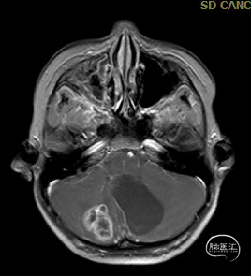

术后MRI

枕下后正中开颅小脑肿瘤切除术

术后病理